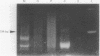

AIMS: (1) To assess the clonality of tumour cells in two patients with mycosis fungoides who subsequently developed Hodgkin's disease; and (2) to determine whether there is a clonal relation between these two disorders. METHODS: Cutaneous tissue samples involved by mycosis fungoides and lymph nodes involved by Hodgkin's disease from both patients were investigated by immunohistochemistry and the polymerase chain reaction. RESULTS: Mycosis fungoides tumour cells in both patients expressed multiple T cell associated antigens; Reed-Sternberg (RS) cells had the null phenotype. T cell receptor gamma chain genes were clonally rearranged in mycosis fungoides cells but not in RS cells, including variants, in both patients. In the patient with intermediate transformation to large cell lymphoma, immunoglobulin heavy chain genes were rearranged in the cutaneous tumour, but not in the lymph node involved by Hodgkin's disease. CONCLUSION: The divergent antigen expression and gene rearrangements observed in these two patients strongly suggest that Hodgkin's disease and mycosis fungoides are not derived from a single tumour cell clone.